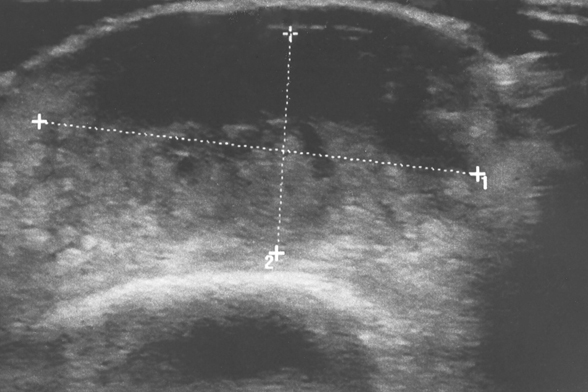

Learn more about ultrasound guided injections and hyaluronic (gel) injections.